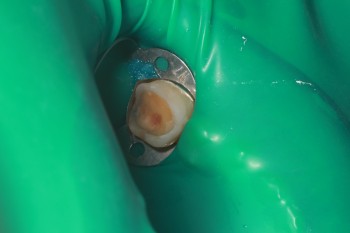

15 работ в портфолио

Специализация: терапевтическая стоматология, хирургическая стоматология, ортопедическая стоматология Особые навыки: Лечение трудно проходимых корневых каналов под микроскопом, высокохудожественные реставрации жевательной группы зубов, удаление зубов мудрости.